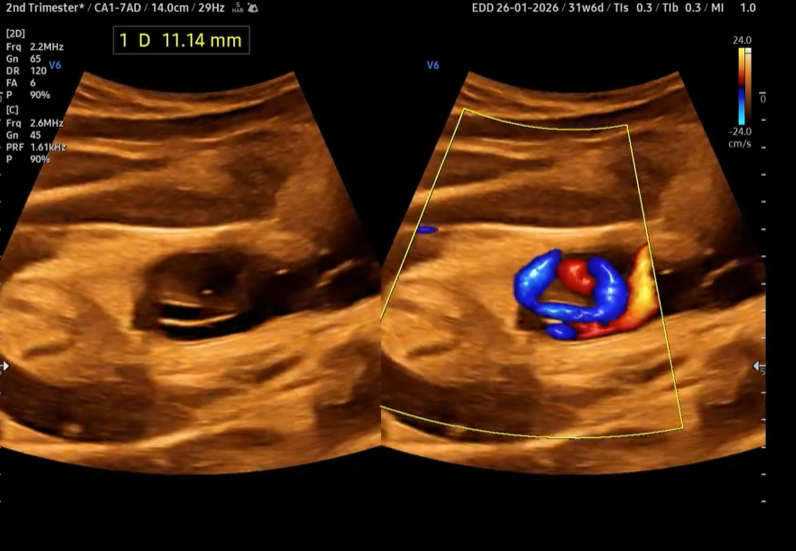

Xoắn dây rốn (Umbilical Cord Coiling)